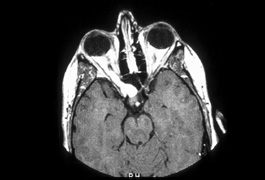

Anterior visual pathway gliomas account for the majority of intrinsic optic nerve tumors in childhood (Figs. 11, 12). Although they are true neoplasms, malignant features are extraordinarily rare in the pediatric population (see Chapter 5). Dutton58 provided a thorough review of this subject. When the glioma is initially confined to the optic nerve alone, the mortality rate is 5%. However, when the hypothalamus is involved, survival is less than 50% in some series. With a typically indolent course, these tumors generally can be managed conservatively, especially when confined to the optic nerve. Hoffman et al59 reviewed 62 cases of optic pathway/hypothalamic gliomas over a 14-year period, with 48 of these exhibiting relative stability with only visual defects: six patients had significant neurologic abnormalities, and eight died. Gayre et al60 reported a series of 42 patients with optic gliomas seen over 28 years at a single institution. Two-thirds were female, and slightly over half had neurofibromatosis type I (NF-1). Presenting signs and chiasmal involvement were similar in both NF (+) and NF (–) groups, the latter usually occurring within the first year after diagnosis. Regardless of treatment, the eye with better vision tended to remain stable over the long-term (and vision in the poorer eye often declined). Spontaneous regression of optic gliomas with visual improvement also has been reported.61,62

Fig. 11. Magnetic resonance imaging scans of optic gliomata. A. Marked enlargement of optic chiasm on coronal image. B. T1-weighted, gadolinium-enhanced image showing enlargement and marked enhancement of the right optic nerve and chiasm.